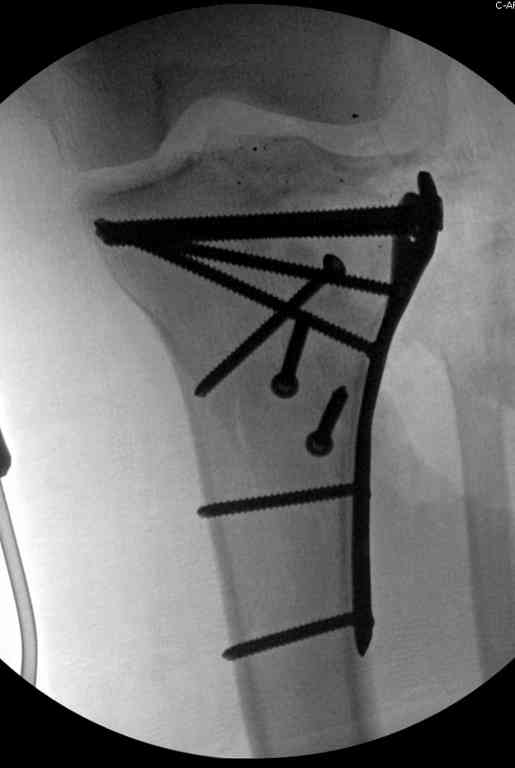

На первом этапе с задачей справляется наружный фиксатор, который создает благоприятные условия для закрытия ран и контролирует длину конечности. На данном этапе рекомендована КТ, чтобы увидеть топографию фрагментов для расчета направления фиксирующих элементов.

Здесь применение материала Plexur http://www.plexur.com для пластики при дефектах кости у больной с огнестрельной раной латерального тибиал плато с повреждением малоберцового нерва. Несмотря на интактный медиальный мышелок, для профилактики от вальгуса установлен АВФ и сделана ангиограмма.

После нескольких обработок и вакуумирования, поэтапно сделана фиксация тибиального бугра шурупами. И окончательную фиксацию закончили латеральной пластиной для тибиал плато и установкой пластического материала.